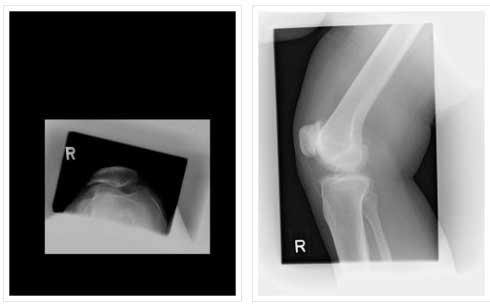

PATELLOFEMORAL ARTHRITIS IN- 40 YEAR OLD FEMALE

PATELLOFEMORAL REPLACEMENT-POSTOP

BILATERAL PATELLOFEMORAL REPLACEMENT

BILATERAL PATELLOFEMORAL REPLACEMENT

LATERAL VIEW